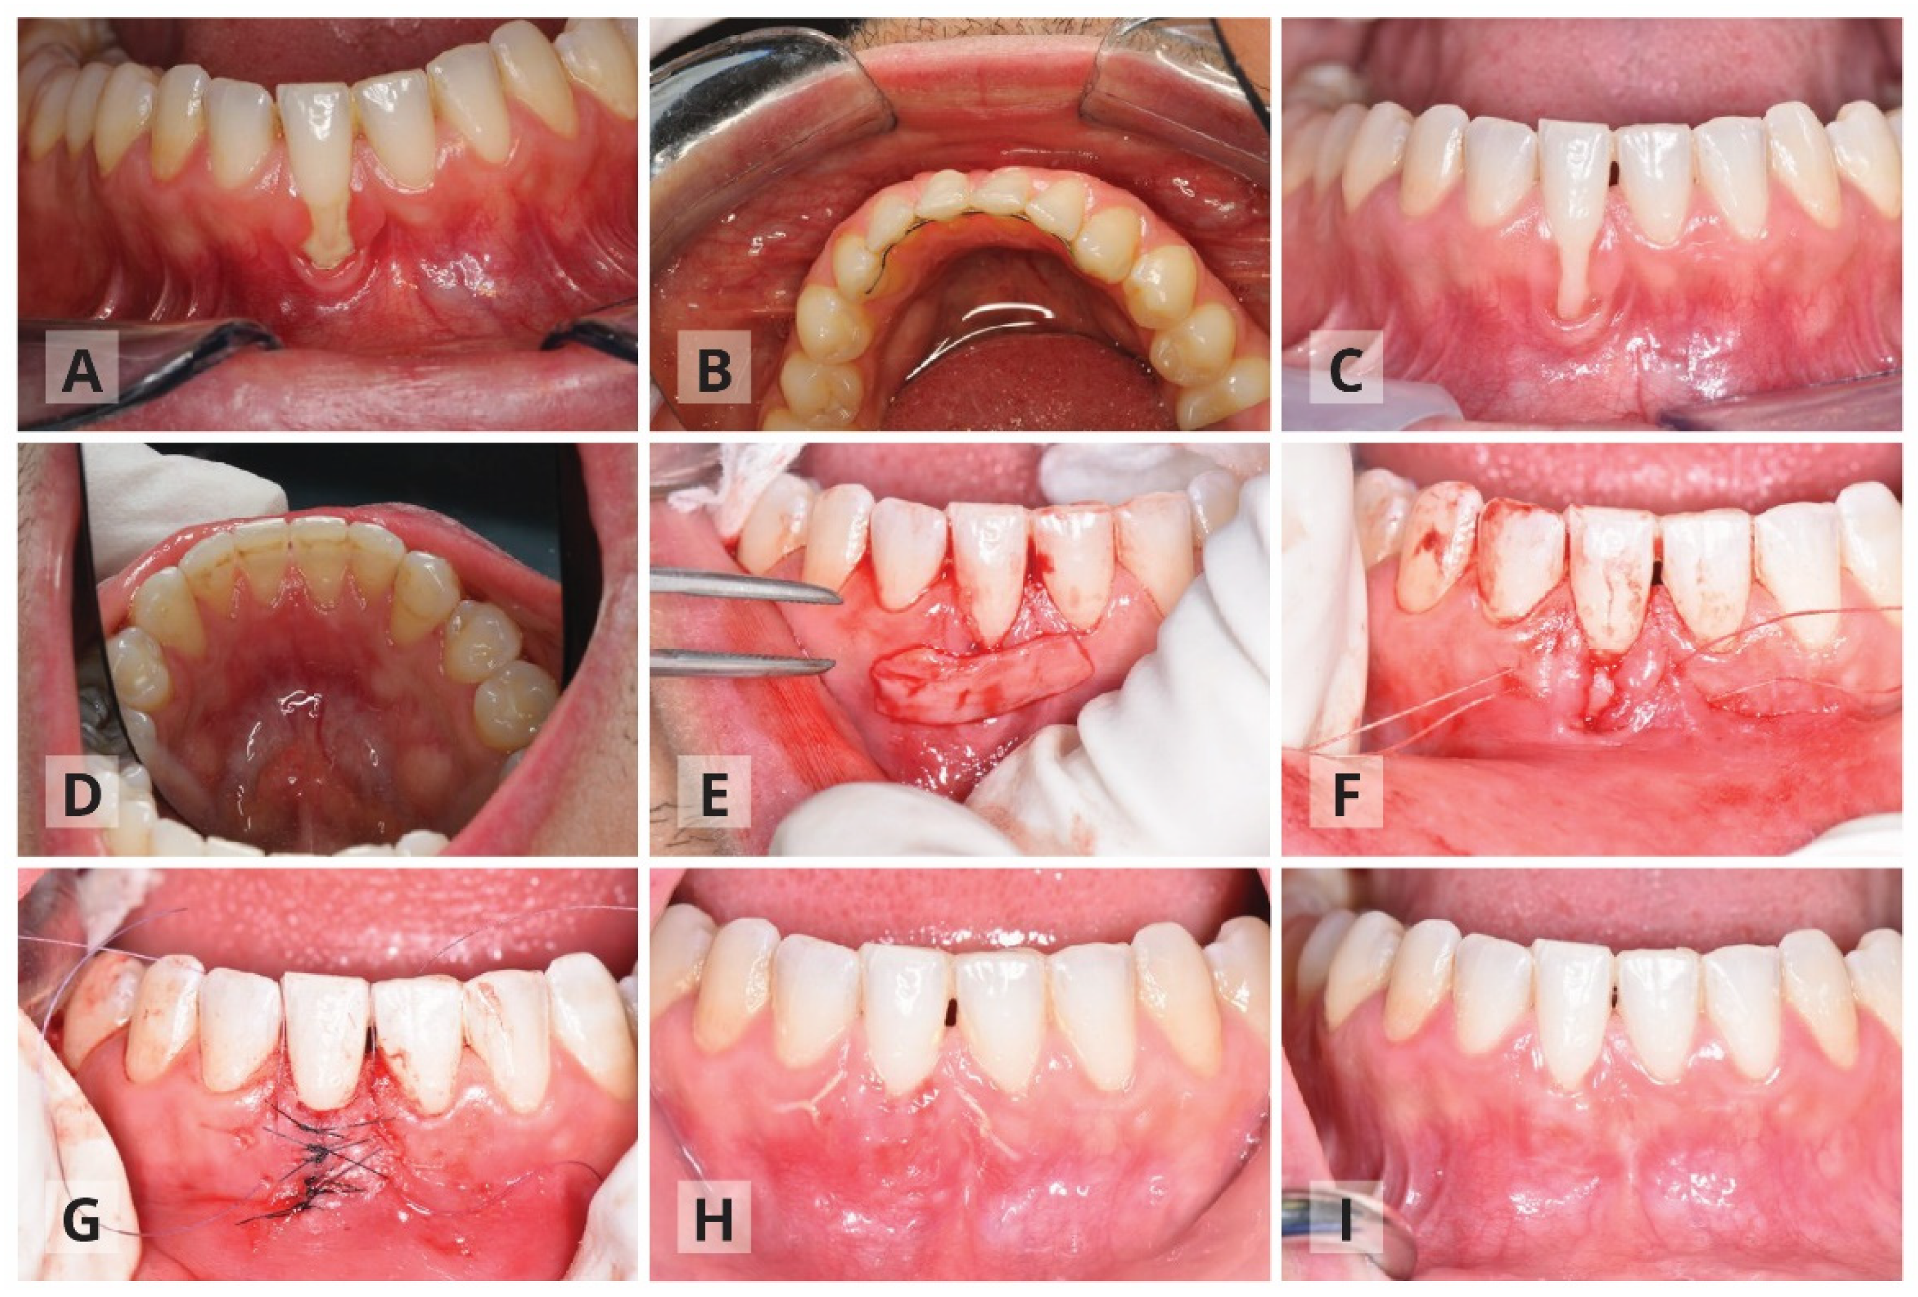

The Surgical Procedure: Modified Tunnel Double Papilla Procedure for Root Coverage